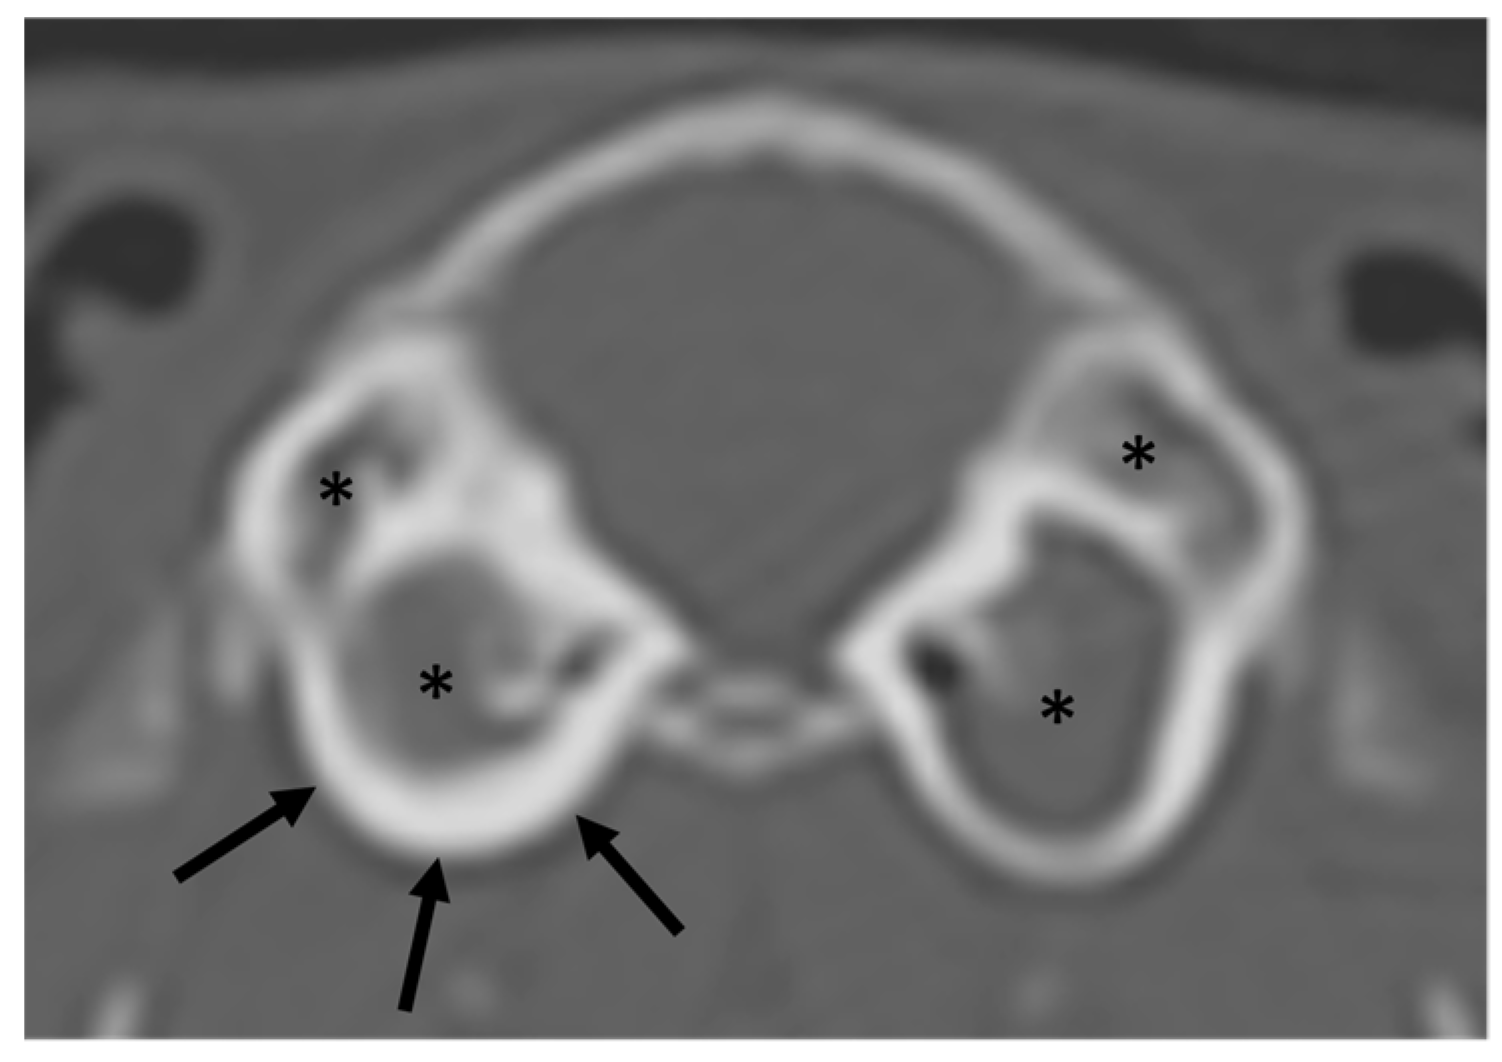

| Bulla tympanica | Increased attenuation (11/34) | Enlargement (0/0) | Thickening of the wall (6/16) | Lysis or irregularities of the wall (2/0) |